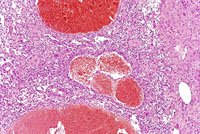

Another example of a hemangiosarcoma.

This hemangiosarcoma is poorly demarcated from surrounding parenchyma and consists of dilated blood-filled spaces and sheets of proliferating endothelial cells.